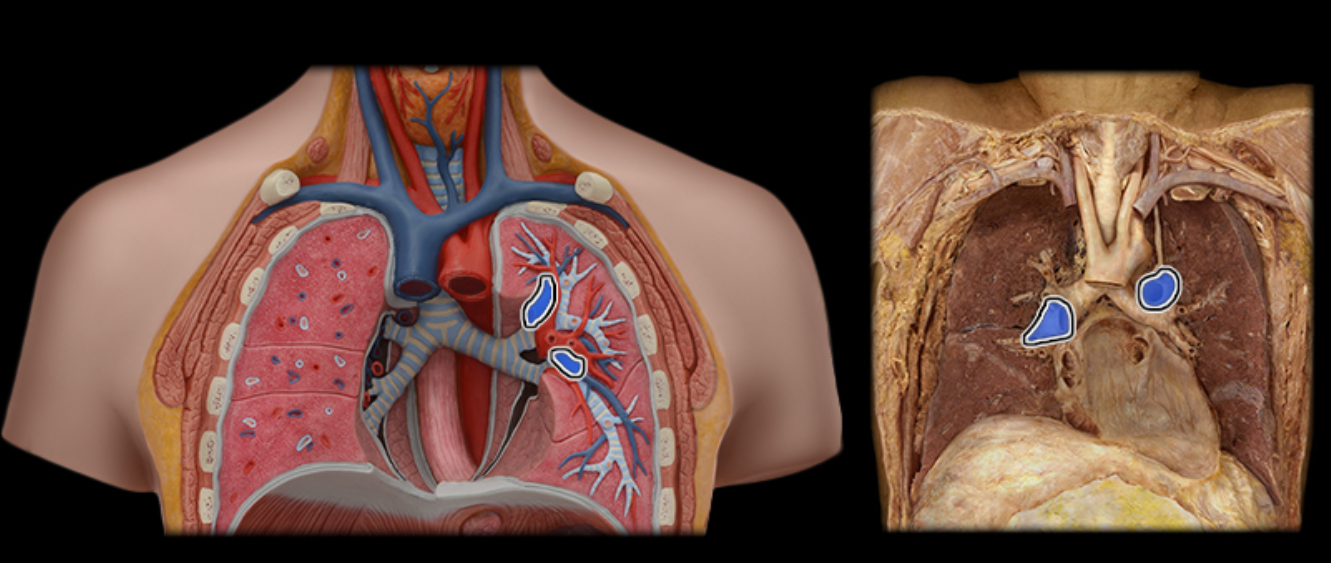

The structure at the tip of the arrow contains

deoxygenated blood of the pulmonary circuit

Brachiocephalic v.

Common carotid a.

Internal jugular v.

Pulmonary a.

Pulmonary vv.

Subclavian v.